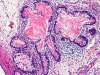

The excised specimen consists of multiple fragments of tan, soft tissue, 5.0 x 2.0 x 1.0 cm in aggregate, for examination. On gross examination, neither calcified tissue nor hair were found. An intraoperative frozen section and cytologic preparation was performed which revealed mature intestinal element, skin and small amount of hair. No germinoma element, yolk sac tumor (endodermal sinus tumor) element, embryonal cell carcinoma, or immature teratoma component was present in multiple specimens submitted for frozen section. Although a minute amount of hair was revealed on the frozen section, gross examination of the submitted tissue does not identify any hair or calcified tissue. An intraoperative diagnosis of teratoma with only mature element present was made.

The entire specimen was submitted for histologic examination. The bulk (over 99%) of the tumor was composed predominantly of mature intestinal elements (Panel A, B, and C) and skin, respiratory type mucosa, cartilage, and small amount of mature neural parenchymal tissue of the central nervous system (Panel D and E). Neither immature nor malignant elements are present. Small microscopic foci of well demarcated, neural parenchymal tissue with increased atypia (arrow in panel F) are noted. On higher magnification (Panel G and H), these areas contain large, bizarre appearing cells with dark chromatin but no prominent nucleoli. There are also scant multinucleated cells and mineralized substances (arrow in Panel H). Another example of these foci is illustrated in Panel I, J, and K. These atypical foci comprised less than 1% of the volume of the tumor. They are all microscopic in size and show no evidence of expansion or invasion into the surrounding tissue.